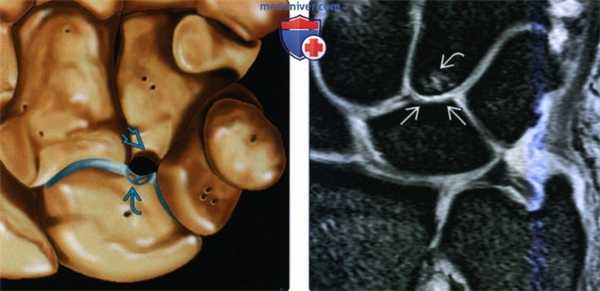

(Слева) На фронтальном рисунке показаны повреждения, характерные для синдрома сдавливания крючковидной и полулунной костей. Полулунная кость имеет крючковидную (медиальную) суставную поверхность, которая сочленяется прямо с крючковидной костью. Хрящ проксимальной поверхности крючковидной кости отсутствует на всю толщину и образуется субхондральная киста.

(Справа) На фронтальной МРТ PDBИ FS определяется II тип полулунной кости с длиной крючковидной суставной поверхности 5 мм. Суставной хрящ дистальной поверхности полулунной кости и проксимальной поверхности крючковидной кости истончен с реактивным субхондральным отеком костного мозга в крючковидной кости.